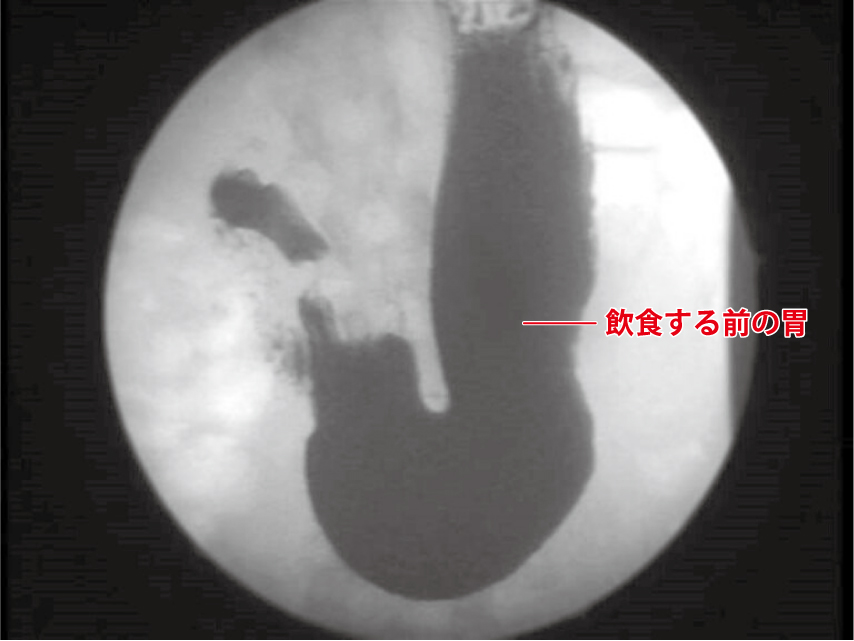

飲む前

▲通常は、「ぜん動運動」も活発でなく、ほとんど胃は収縮していません。